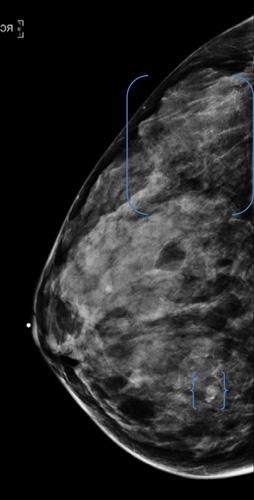

For her study, Arleo and a team of researchers analyzed data on screening mammography at New York – Presbyterian Hospital — Weill Cornell Medical College between 2007 and 2010. Over the four years, 43,351 screening exams were performed, which led to the detection of 205 breast cancers.

"Nearly 20 percent of cancers detected with screening mammography were found among women in their 40s, Arleo said. "It seems unacceptable to potentially miss nearly 20 percent of the breast cancers we are identifying. This, in our view, would represent a substantial degree of under-diagnosis."

Of the women screened in the study, 14,528, or 33.5 percent, were between the ages of 40 and 49. Of the 205 breast cancers detected, 39 (19 percent) were found in the 40-49 age group. Of those cancers, more than 50 percent (21 of 39) were invasive. Only three of the women between the ages of 40 and 49 diagnosed with cancer had a first-degree relative with pre-menopausal cancer.

"Our data favor the American Cancer Society recommendations of annual mammograms starting at age 40," Arleo said.